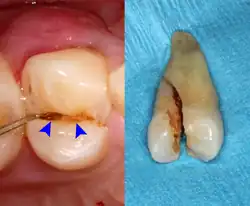

Cracked tooth syndrome refers to a highly variable[30] set of pain-sensitivity symptoms that may accompany a tooth fracture, usually sporadic, sharp pain that occurs during biting or with release of biting pressure,[31] or relieved by releasing pressure on the tooth.[10]: 24 The term is falling into disfavor and has given way to the more generalized description of fractures and cracks of the tooth, which allows for the wide variations in signs, symptoms, and prognosis for traumatized teeth. A fracture of a tooth can involve the enamel, dentin, and/or pulp, and can be orientated horizontally or vertically.[10]: 24–25 Fractured or cracked teeth can cause pain via several mechanisms, including dentin hypersensitivity, pulpitis (reversible or irreversible), or periodontal pain. Accordingly, there is no single test or combination of symptoms that accurately diagnose a fracture or crack, although when pain can be stimulated by causing separation of the cusps of the tooth, it's highly suggestive of the disorder.[10]: 27–31 Vertical fractures can be very difficult to identify because the crack can rarely be probed[10]: 27 or seen on radiographs, as the fracture runs in the plane of conventional films (similar to how the split between two adjacent panes of glass is invisible when facing them).[10]: 28–9

The prognosis for a cracked tooth varies with the extent of the fracture. Those cracks that are irritating the pulp but do not extend through the pulp chamber can be amenable to stabilizing dental restorations such as a crown or composite resin. Should the fracture extend though the pulp chamber and into the root, the prognosis of the tooth is hopeless.[10]: 25